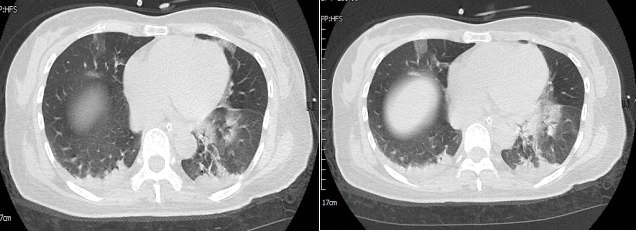

胸部CT:双肺多发斑片状磨玻璃影,双肺下叶胸膜下片状实变影(图2),考虑炎性病变,病毒性肺炎不除外。

图2:患者胸部CT

患者入院肺CT提示:双肺多发斑片状磨玻璃影,双肺下叶胸膜下片状实变影,患者新冠病毒核酸阳性,有乏力、咳嗽、咳痰、发热症状,考虑病毒感染所致肺间质改变,结合患者上述现病史、体征、查体和实验室检查结果,首先考虑患者意识改变为糖尿病性高渗性昏迷可能大,感染为诱发因素,患者病情进展恶化快伴呼吸衰竭,给予报病危、气管插管呼吸机辅助通气、哌拉西林钠他唑巴坦钠4.5g q8h抗感染、奥美拉唑40 mg/d,抑酸护胃预防应激性溃疡、胰岛素泵入降血糖、适当补液、半张氯化钠补液、鼻饲补钾、鼻饲温开水和糖水纠正高钠高氯、肠内营养支持治疗,辅以平喘、化痰、纠正低蛋白、祛痰等对症治疗。

该患者中年女性,既往糖尿病、脑出血术后病史,平素未规律监测血糖,此次急性起病,以呼吸道症状发病,表现为乏力、咳嗽、咳痰、发热不适。查体:双肺呼吸音粗,可闻及湿啰音。胸部CT:双肺多发斑片状磨玻璃影,双肺下叶胸膜下片状实变影,疾病进展迅速,出现意识改变和急性呼吸衰竭,入院诊断考虑重症肺炎,间质性肺改变,该患者既往无肺部基础疾病,多种病因包括感染、结缔组织病、肿瘤或药物肺损伤等,均可引起急性肺损伤,表现为肺间质炎症、纤维化或弥漫性肺损伤改变。

COVID-19主要表现为发热、干咳、咽痛、乏力,以及不典型的上呼吸道症状如肌痛、腹泻、结膜炎、嗅觉味觉减退等,重症患者多在1周内出现呼吸困难和低氧血症,严重者出现急性呼吸窘迫综合征(ARDS)/多器官功能障碍综合征(MODS)。胸部影像学以磨玻璃影或实变为主要表现,可有网格和索条影,但相对较轻,蜂窝或牵张性支气管扩张等肺结构破坏征象不明显,该患者胸部影像学以双肺弥漫性渗出改变为主要表现,临床上急性起病,伴有发热、乏力、咳嗽、咳痰,符合COVID-19临床表现,且患者核酸阳性,入院后完善血培养、痰培养、真菌培养、呼吸道病原学等检查均为阴性,患者既往无心肺基础疾病,无口服特殊药物病史,且此次起病急剧,故考虑COVID-19所致间质肺改变。